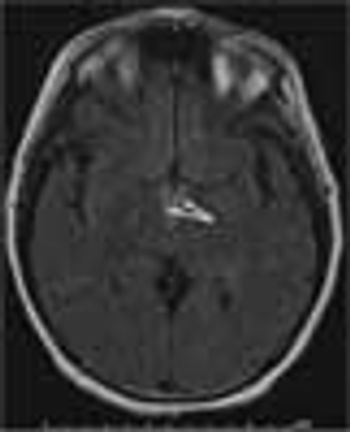

A 37-year-old man was brought to the emergency department (ED) after he had 2 near-syncopal events. The first occurred in the morning and rapidly resolved; the second occurred later in the day at work. The night before he had a headache and neck pain. In the ED, he reported left arm and leg weakness and was noted to have left facial droop.